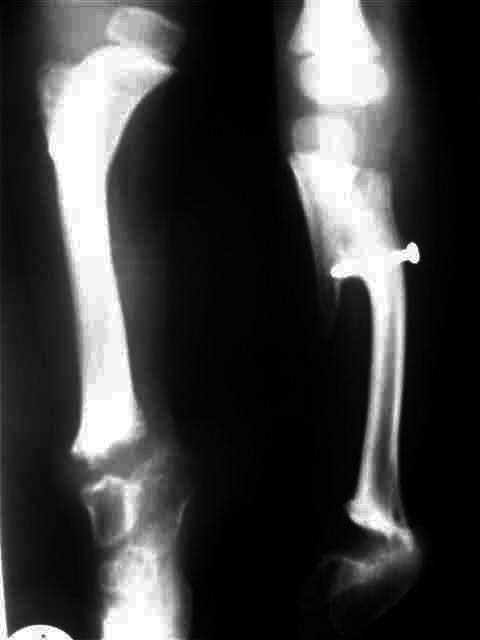

Уважаемые коллеги,Ребенок 4 лет с врожденной гемимелией б/б кости справа.

Первые две операции сделаны в годовалом возрасте - проксимальный тибио-фибулярный синостоз и транспозиция дистального отдела малоберцовой кости на таранную кость.В настоящее время - пользуется ортопедической обувью, компенсирующей 6 см укорочение конечности, нога опороспособна и безболезненна.Рг - компенсаторная гипертрофия малоберцовой кости, состоявшийся синостоз б/б и м/б.Вопрос: когда следует начинать коррекцию длины в аппарате?Заранее спасибо за рекомендацииЕвгений И Чекашкин

Сейчас ребенку 4 года, укорочение 6 см. Существует мнение о начале коррекции в аппарате не ранее 5 летнего возраста, кость становится прочнее, меньше риск миграции спиц. Хотя и на современных Рг кость выглядит вполне *зрелой*.

К сожалению, после осмотра весь пакет с Рг родители забрали с собой. Описание Рг: В принципе, голеностопного сустава (как анатомического образования) у ребенка не было сформировано, поэтому при росте м/б кости происходило * выталкивание* стопы медиально с её супинацией (начальные снимки). Поэтому, чтобы яредотвратить усугубление деформации стопы, мы решили сопоставить м/б кость с таранной и фиксировали спицами и гипсовой повязкой. На том этапе сознательно на артродез не пошли, рассчитывая, что фиброз в зоне контакта костей позволит сохранить межфрагментарную подвижность, облегчающую ходьбу, и не ошиблись. На данный момент подвижность в зоне контакта малоберц.-таранная костей в пределах 30 градусов (пассивные движения) активные практически отсутствуют, можно думать и о мышечной аномалии- выражены только сгибатели и пронаторы стопы.

Я планирую удлинять за счет голени - остеотомия на уровне тиб-фиб синостоза, поскольку удлинение за счет бедра приведет к разновеликим коленкам, длину мы восстановим, а вот соосность пострадает. Следующий осмотр назначил через 6 мес - чтобы оценить природную скорость продольного роста правой голени и более определенно планировать коррекцию или пойти на гиперкоррекцию. Что вы думаете по этому поводу?